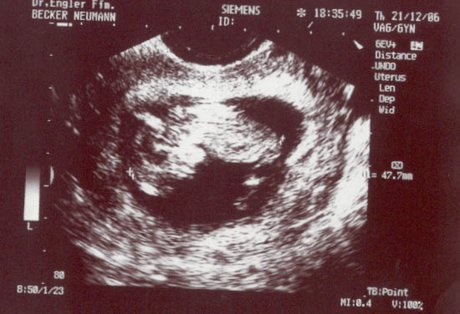

Johanna is coming soon